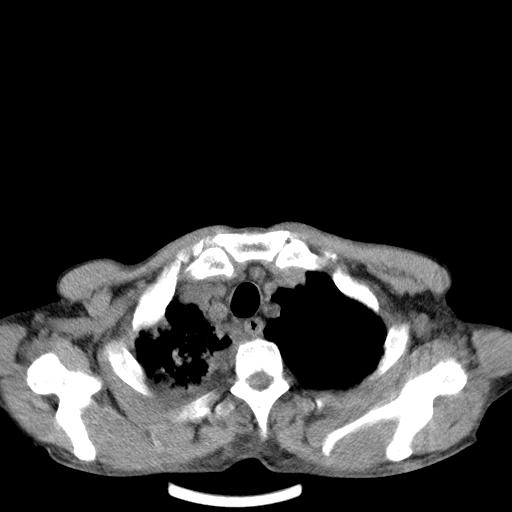

男性 75  咳嗽 一周前发热最高达39

右肺继发型tb并右侧tb性胸腔炎,右侧胸腔大量积液并右下肺膨胀不全,慢支肺气肿、多发肺大泡。建议抽胸水实验室检查并复查排除恶性在占位。

右上肺继发型肺结核,右胸腔中等量积液。

左上肺大泡。

结核的基础上有纵隔淋巴结肿大,右侧有胸水,但右侧纵隔反而窄,说明有肺有不张。

再就是右下肺有块影,和不张混合,还是不能除外肺癌。

补充材料,患者2月份ct片大致正常,双侧胸腔积液,2月份抽胸水未发现ca细胞,现患者发热,痰多,各气管通畅,